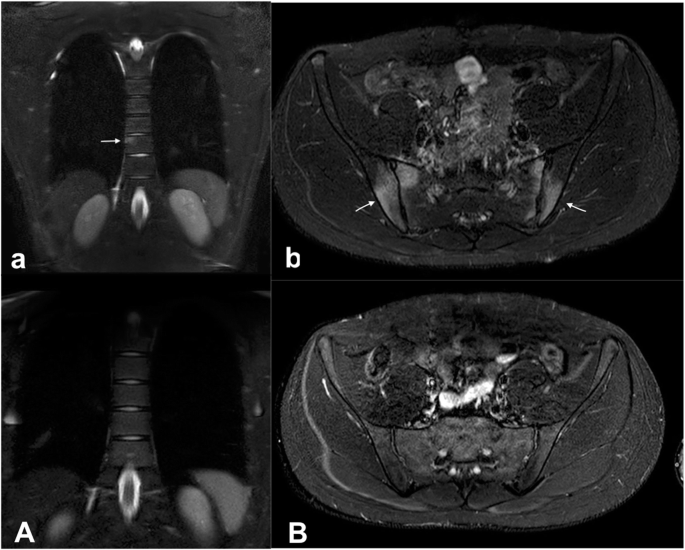

Ten weeks after starting isotretinoin, the patient experienced increasing low-back pain with progressive inability to walk and restriction of daily activities. At admission to the emergency department, he was suffering and unable to walk. Physical examination revealed a decreased axial range of movement, sacroiliac pain and severe nodulocystic acne with abscesses on face, neck and thorax. Laboratory investigations revealed systemic inflammation (CPR 7.15 mg/dl [normal range < 0.5 mg/dl], ESR 84 mm/h [normal range < 30 mm/h], WBC 14,950/mmc, 70% neutrophils). All rheumatologic parameters including complement and autoantibodies were within normal range. The patient tested negative for HLA-B27 typing. Culture of the pustular lesions was positive for Staphylococcus aureus. Antibiotic therapy with clindamycin was introduced and isotretinoin was interrupted. Pelvis and hip X-ray was unremarkable. Magnetic resonance imaging (MRI) showed moderate bone marrow oedema and osteitis of transverse process of fifth lumbar vertebra (Fig. 1a) and symmetrical sacroiliitis (Fig. 1b). The association of acne fulminans and osteitis suggested the diagnosis of SAPHO syndrome. Whole body MRI confirmed this hypothesis revealing anterior chest wall, in particular coronal views showed sternoclavicular and costoclavicular osteitis, and axial involvement, including sacroiliac joint and spine. Consequently, intravenous antibiotics were interrupted and, NSAIDs and oral rifampicin were started, in order to control the inflammatory status and the cutaneous lesions, respectively. Despite the specific treatment, the depressive disorder was persisting along with the other complaints. Nevertheless, during the following weeks osteoarticular involvement and cutaneous manifestations worsened and gluteal bilateral HS appeared. Therefore, ADA was subcutaneously administered at the dosage of 40 mg/dose every 2 weeks. After 4 weeks of treatment a progressive improvement both of cutaneous lesions and osteoarticular symptoms was reported and ADA administration interval (at the same dose of 40 mg) was extended to 4 weeks. After six months of favourable ADA treatment, the boy experimented a relapse of osteoarticular symptoms. Therefore, ADA was administered again every 2 weeks obtaining a long-lasting remission. An MRI performed 12 months later, has shown no evidence of abnormal vertebral bone marrow signal (Fig. 1a), sterno-clavear or sacroiliac effusions (Fig. 1b). After 24-months treatment with ADA, the disease maintains complete remission. In Fig. 2 we show cutaneous lesions on the face, on the back and on the sternal region before and after ADA treatment. On the contrary, the depressive mood disorder persists and negatively affects the quality of patient’s life.